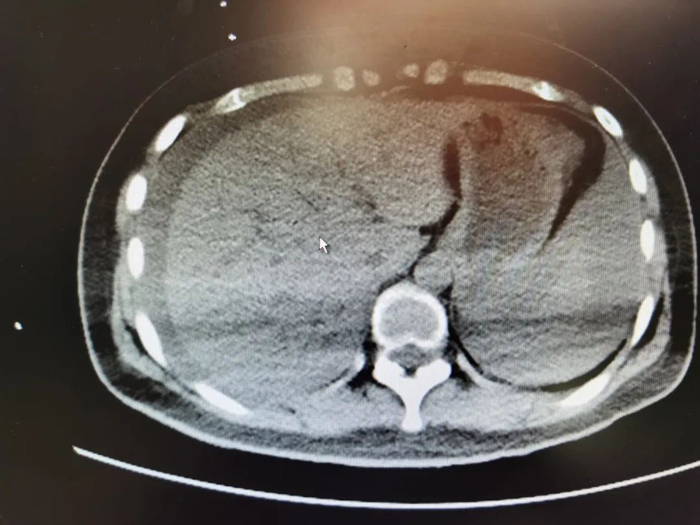

下图便是患者的检查资料之一,可见腹腔已有大量积液。

虽然这位病人最终通过手术得以续命,但我们不仅想要,如果病人在“腹痛腹泻”一开始便来到医院,而不是误以为自己是“拉肚子”耽误了五个多小时的话,可能便不会如此惊心动魄了。